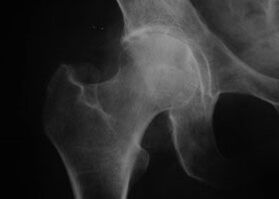

Κοξάθρωση, αρθροπάθεια της άρθρωσης του ισχίου

Με αυτή τη νόσο παρατηρείται μια κλασική κλινική εικόνα αρθρώσεως.

Το πρώτο σύμπτωμα της κόξαρθρωσης είναι η ενόχληση στην άρθρωση του ισχίου μετά από φυσική δραστηριότητα.

Με την προοδευτική κοξάρθρωση, ο πόνος αυξάνεται, εμφανίζεται δυσκαμψία και περιορισμένη κινητικότητα.

Οι ασθενείς με σοβαρή μορφή κόξαρθρωσης περιποιούνται το πάσχον άκρο, αποφεύγοντας να το πατήσουν και ενώ είναι ακίνητοι, επιλέγουν θέσεις στις οποίες ο πόνος γίνεται λιγότερο αισθητός.